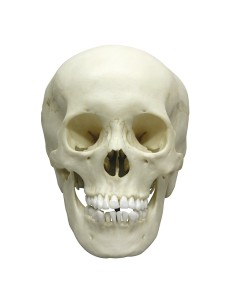

Dal cranio in 22 parti con incastri magnetici ai modelli di colonna vertebrale, da quelli di articolazioni a quelli di cuore, ogni pezzo della nostra collezione è progettato per un’immersione totale nello studio dell’anatomia umana. I nostri modelli, realizzati tramite scansioni di ossa vere, garantiscono un’esperienza tattile autentica e una fedeltà di peso quasi identica agli originali.